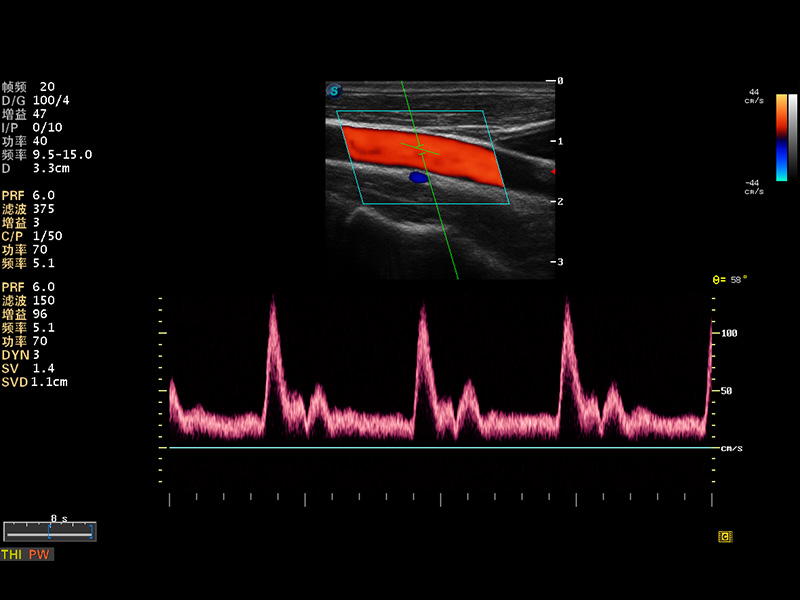

S8 EXP便携式彩色多普勒超声诊断仪是美狮贵宾会官网研发的高端全身应用型便携彩超。高通道的VIS平台融合可视化(Visual)、智能化(Intelligent)和人性化(Smart)的特点,配以美狮贵宾会官网自主研发生产的探头大家族,使您能够快速、准确的获得病人信息,提高工作效率的同时减轻疲劳。